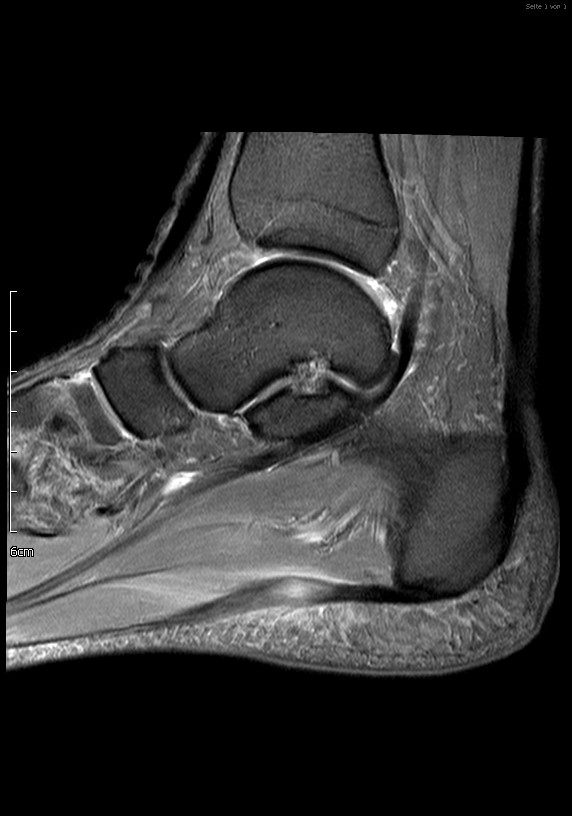

Abb. 2: Teilruptur Plantaraponeurose in der MRT Diagnostik

Eine Teilruptur der Plantaraponeurose kann ursprungsnah oder auch einige cm distal des Ursprungs als Folge einer direkten Gewalteinwirkung auftreten.

Zum Lesen der Bildbeschreibung und zur Vollansicht bitte das Bild anklicken. Bild: Manfred Thomas

In seltenen Fällen findet sich eine komplette Ruptur der Plantaraponeurose als Ursache der Beschwerden (siehe Abb. 3).

Abbildung 3: Komplette Ruptur Plantaraponeurose und Therapie

Abb. 3a: Komplette Ruptur der Plantaraponeurose im MRT als Ursache der Beschwerden deutlich erkennbar.

Abb. 3b: Im präop Röntgenbild kein Fersensporn sichtbar.

Abb. 3c: MRT postoperativ, Knochenanker zur Refixation der Plantarfaszie.

Abb. 3d: Röntgenbild postoperativ, Knochenanker zur Refixation der Plantarfaszie.

Zum Lesen der Bildbeschreibung und zur Vollansicht bitte die Bilder anklicken. Bilder: Dr. Manfred Thomas, Augsburg.